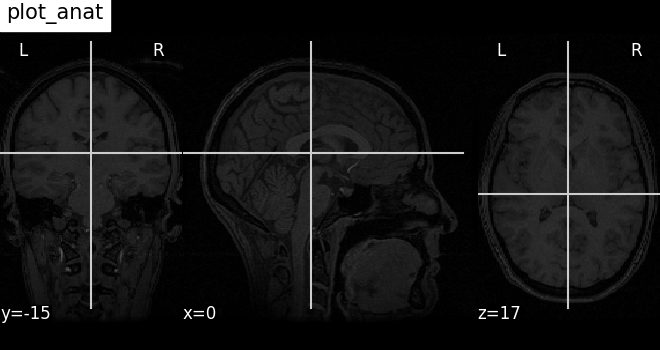

Plotting anatomical images with function plot_anat¶

Visualizing anatomical image of haxby dataset

plotting.plot_anat(haxby_anat_filename, title="plot_anat")

<nilearn.plotting.displays._slicers.OrthoSlicer object at 0x7f3bb4dc48f0>